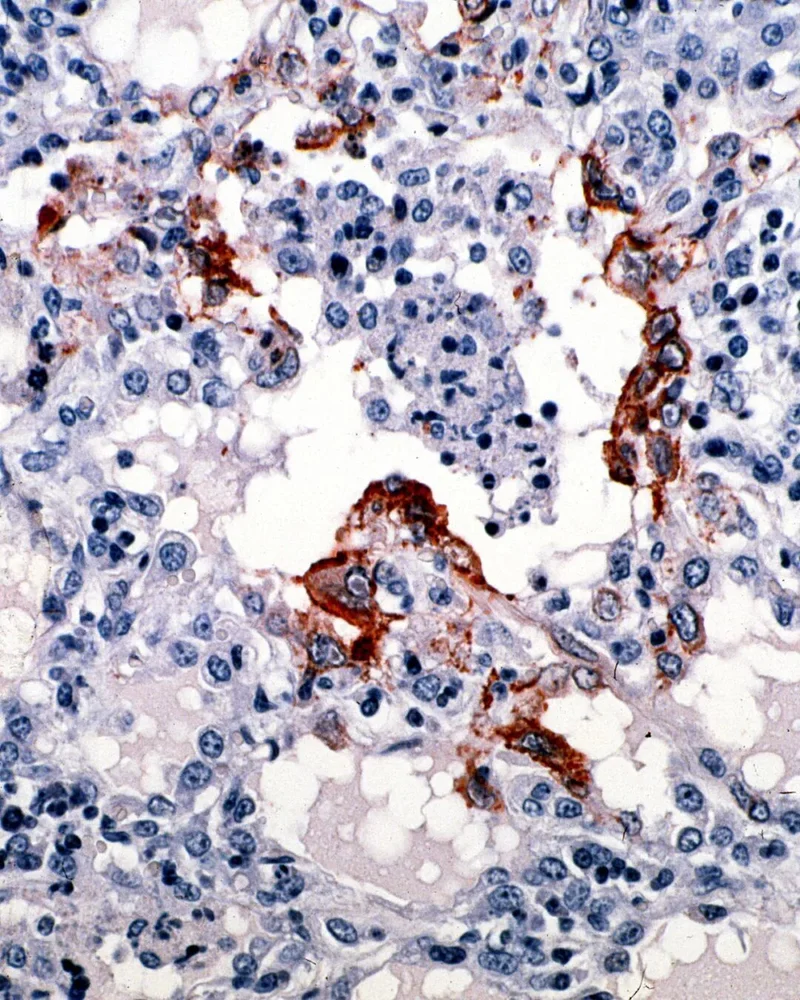

棕色部分即为侵扰肺部的尼帕病毒

这种感染势必会对呼吸系统造成影响

(图:Wikimedia Commons)▼